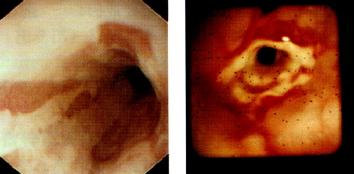

内镜(图3.15)

为诊断食管炎的金标准,既可对食管炎进行观察和分型,又可行食管粘膜活检。

以下为Savary和Miller制定的食管炎内镜下分型:

· Ⅰ期:单个或多个纵行非融合的红斑性粘膜损害,常覆有渗出物,发生于胃食和连接处上方或由连接处延伸开来

· Ⅱ期:融合性糜烂和渗出性粘膜损害,但并未累及食管全周

· Ⅲ期:全周性糜烂及渗出病变,覆盖整个食管粘膜

· Ⅳ期:慢性粘膜损害,如伴或不伴狭窄的溃疡。

图3.15食管远端内镜所见。(a)线状充血糜烂:反流性食管炎。图取自

Cotton & Williams,Practical Gastrointestinal Endoscopy,3rd edn,

1990(Blackwell Science,Oxford),经作者许可。(b)消化性食管狭窄。